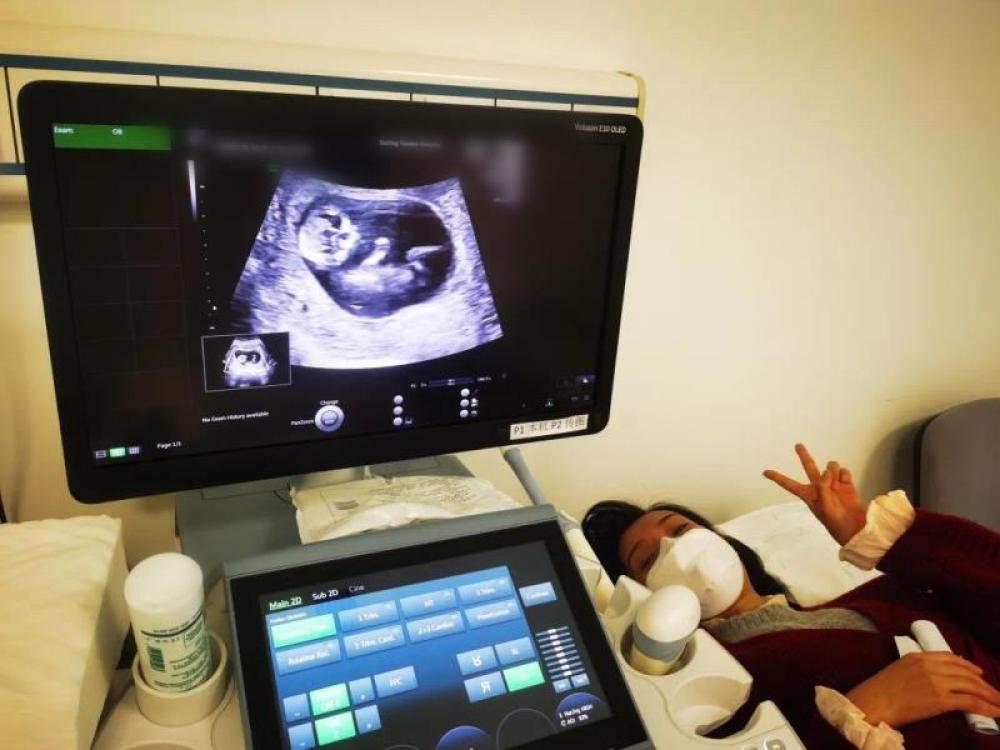

今天一早,妻子去醫(yī)院進行B超檢查,同事用手機拍攝下了B超顯示屏上的畫面,記錄下了這個87天的小家伙第一次“亮相”。

圖為北京天壇醫(yī)院袁磊愛人做B超檢查。

“袁磊,看看你們家寶寶,可愛嗎?”收到同事發(fā)來的視頻,第一眼就看哭了,身邊的同事看完視頻也哭了。

視頻里,這個小家伙好像聽到了外面的召喚,在媽媽的肚子里伸手、踢腿、翻身,用各種動作進行回應……看到他那小胳膊小腿,一種從未有過的幸福感不停地向上涌,眼淚怎么也控制不住。

其實在武漢這么多天,他一直就是我的牽掛,今天終于看到他了,那種感受真是又緊張又激動,雖然還看不清他的樣子,但是已經(jīng)感受到他的活力。